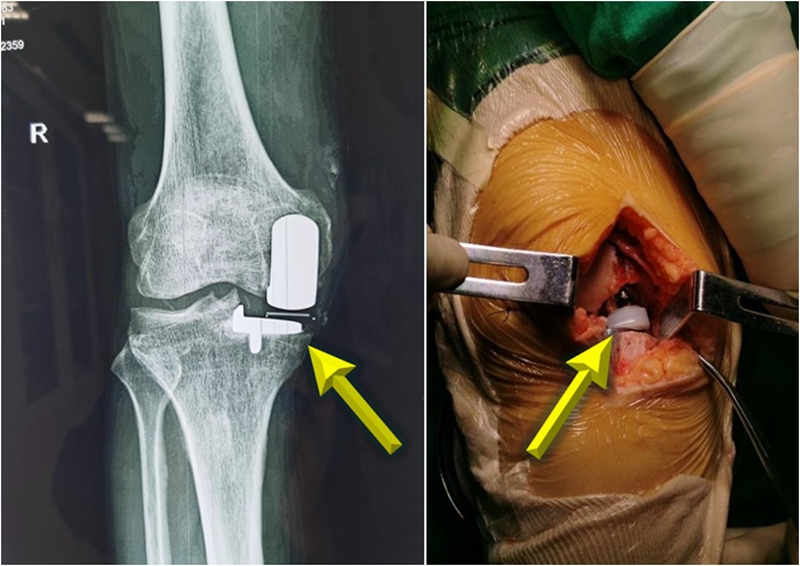

引起UKA失败的原因包括感染、疼痛、垫片脱位、假体周围骨折、无菌性松动、对侧间室关节炎等,其中主要原因为垫片脱位和疼痛。

垫片脱位的机制较为复杂,目前公认的危险因素有多种,其中活动垫片运动轨迹不良是脱位的主要原因。垫片运动学轨迹不良会引起内侧悬出、撞击,垫片旋转、脱位,增加磨损,不明原因膝关节疼痛等问题。这证明运动学轨迹在UKA中极具重要性。

中心线不一致会导致垫片悬出、旋转、脱位,引起撞击和疼痛。